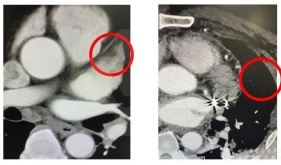

• 经导管主动脉瓣置换术(TAVI)